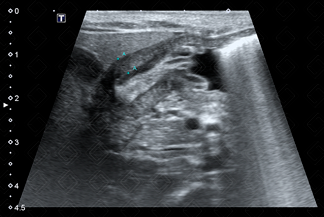

Texto alternativo para a imagem Figura 2. Créditos: Dra. Elazir Mota - Rio de Janeiro/RJ

Descrição das figuras 2 e 3: Ultrassonografia do abdome de lactente com 27 dias de vida evidenciando muscular do piloro espessado (sua muscular media 4 mm) e o canal pilórico alongado. Observe a aparência em alvo do piloro no seu corte transversal, outro sinal clássico de EHP (seta vermelha).